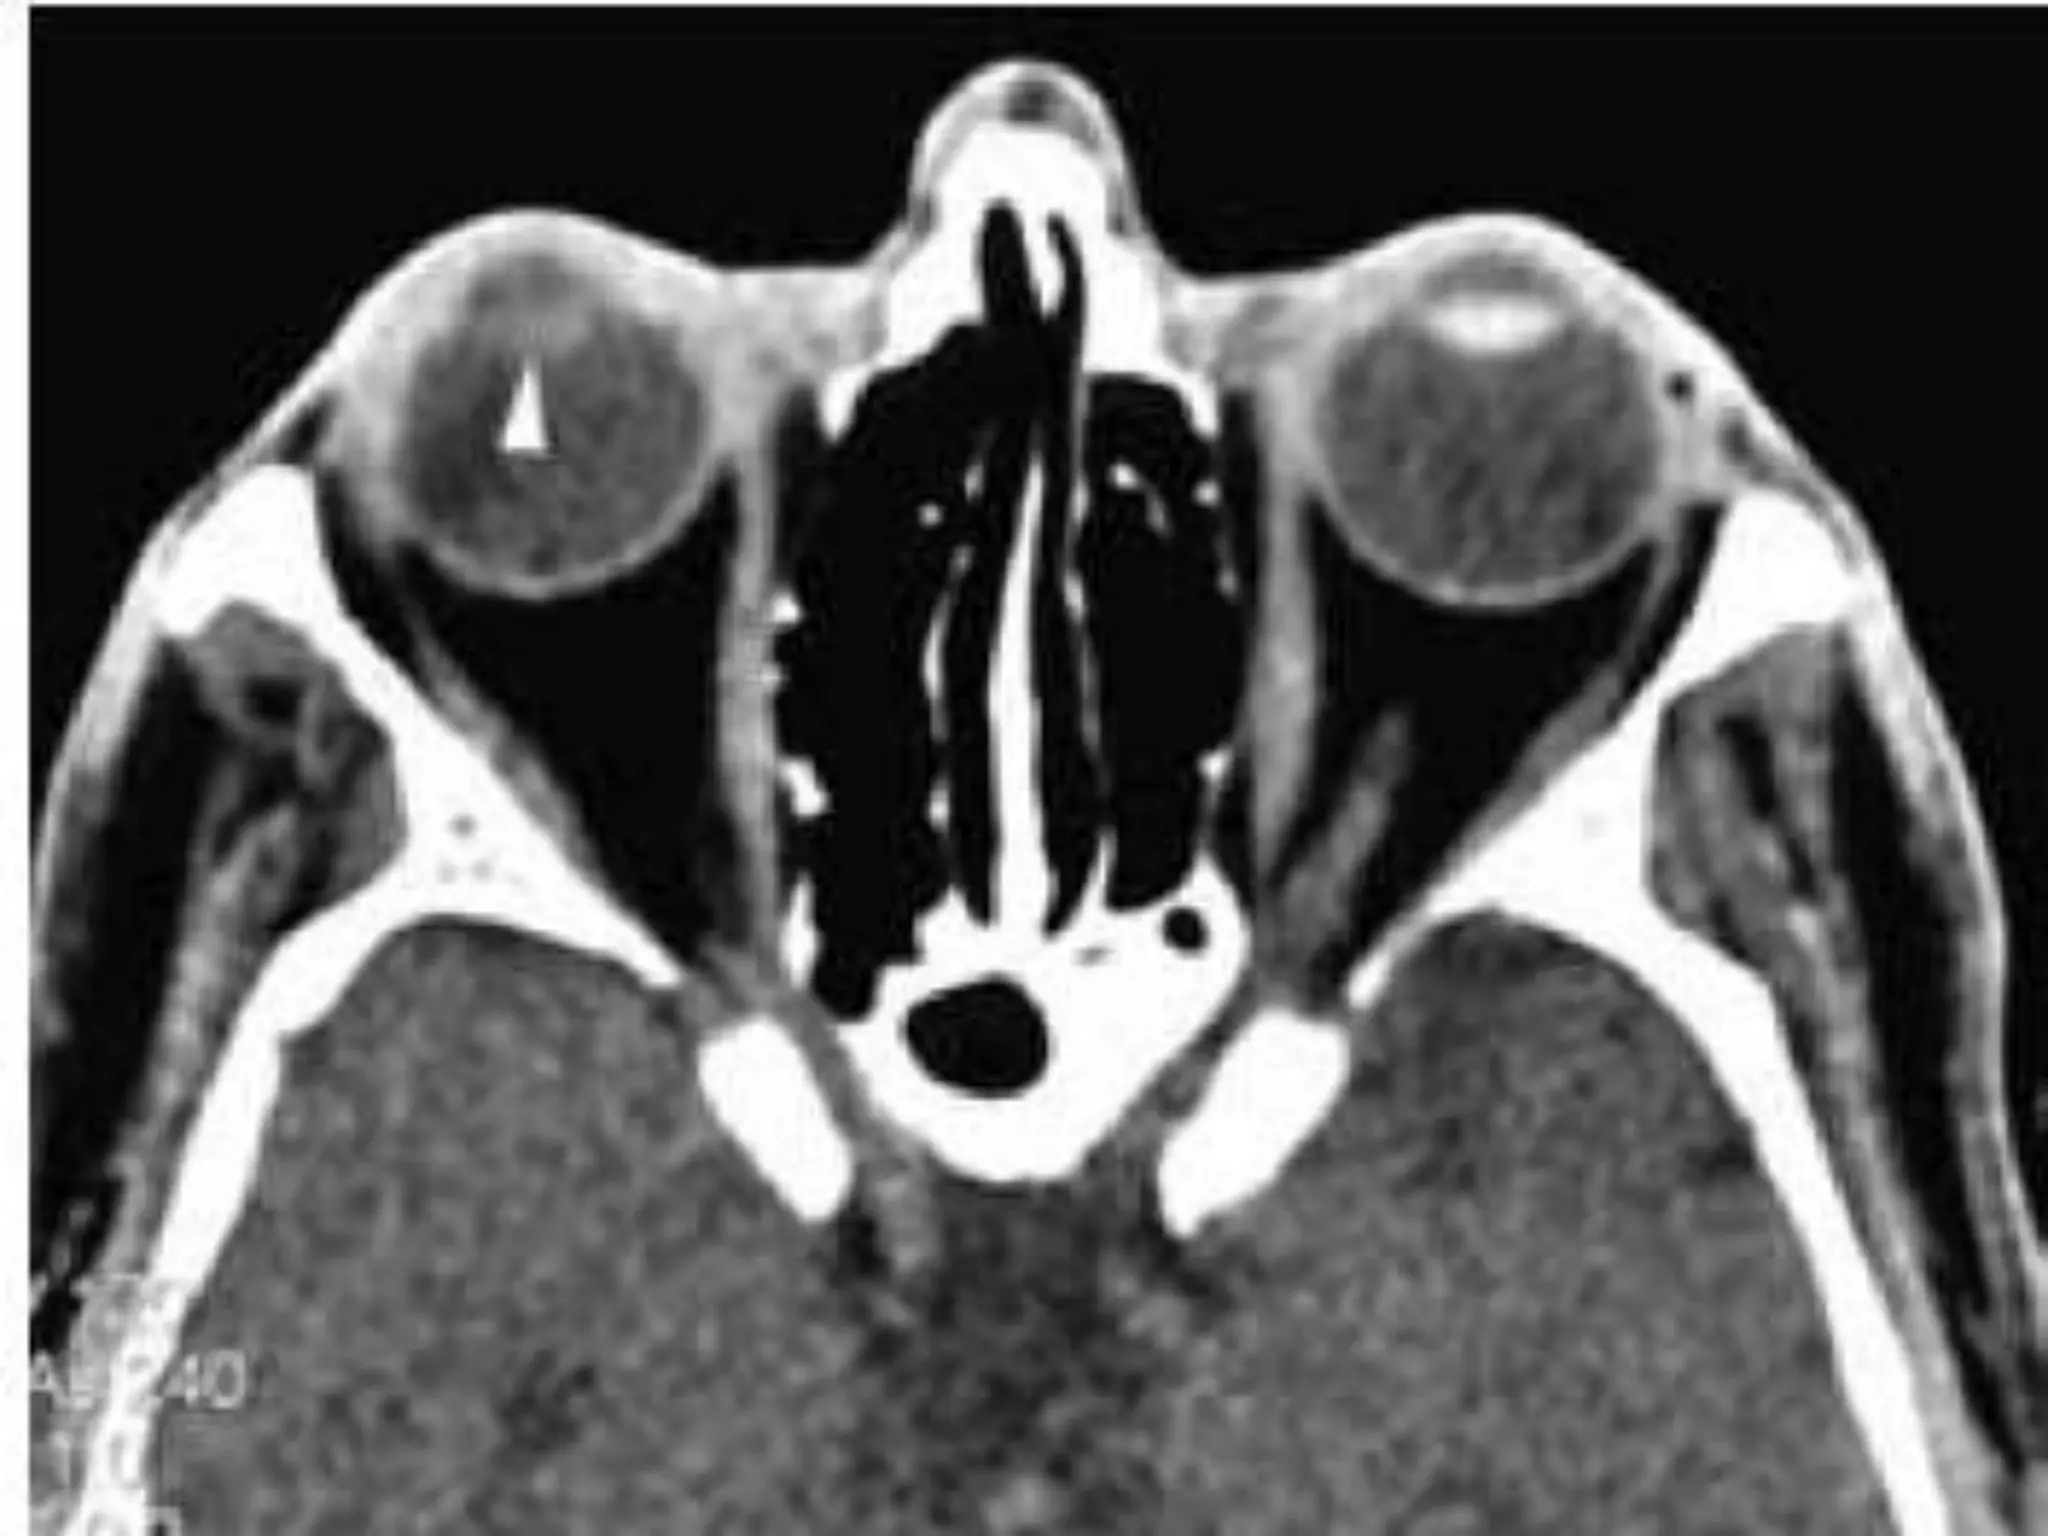

• Imaging -- Heterogeneous poorly marginated

Fig A. Optic nerve Meningiomas. CT -- Enhancement of thickened right

optic nerve with elevation of optic disc (arrowhead).

Fig A. Opticnerve Meningiomas. CT -- Enhancement of thickened right optic nerve with elevation of optic disc (arrowhead). Fig B. Axial T1-weighted post contrast fat-saturated image (B) demonstrates peripheral enhancement of the thickened right optic nerve sheath. Nonenhancing soft tissue within represents the encased optic nerve.